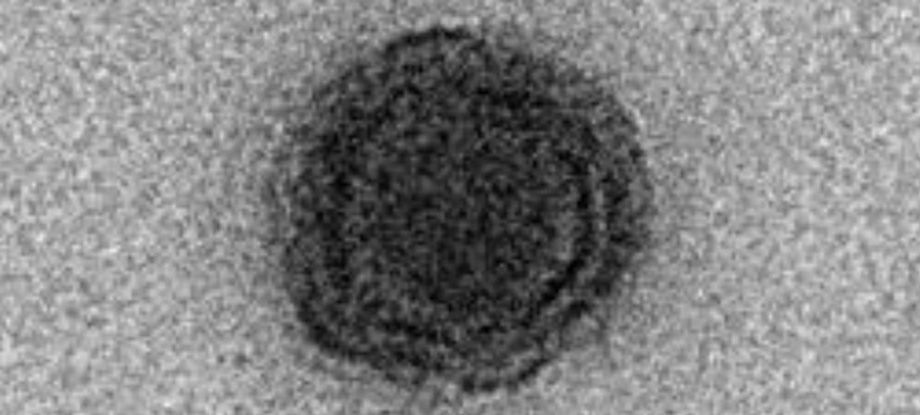

Na preparação da sopa, o morcego é cozido inteiro, com a barriga aberta. Imagens da iguaria se multiplicaram nas redes sociais. Informações do Extra. A disseminação do coronavírus entre humanos na China pode ter origem em morcegos e cobras, como sugere uma análise genética do patógeno que até agora causou 25 mortes e aContinue Reading